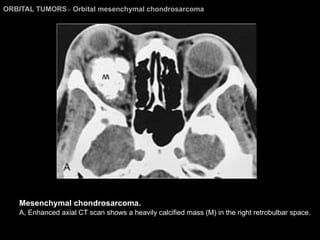

Orbital mesenchymal chondrosarcoma Extremely rare More frequently in young women. Proptosis, with orbital pain, diplopia, and headache. Imaging Findings: Well-defined soft-tissue mass. Mottled, coarse calcification. Moderate, delayed contrast enhancement.  Hypo/iso T1WI and iso on T2WI (to brain).

ORBITAL TUMORS >  Orbital mesenchymal chondrosarcoma Mesenchymal chondrosarcoma.  A, Enhanced axial CT scan shows a heavily calcified mass (M) in the right retrobulbar space.